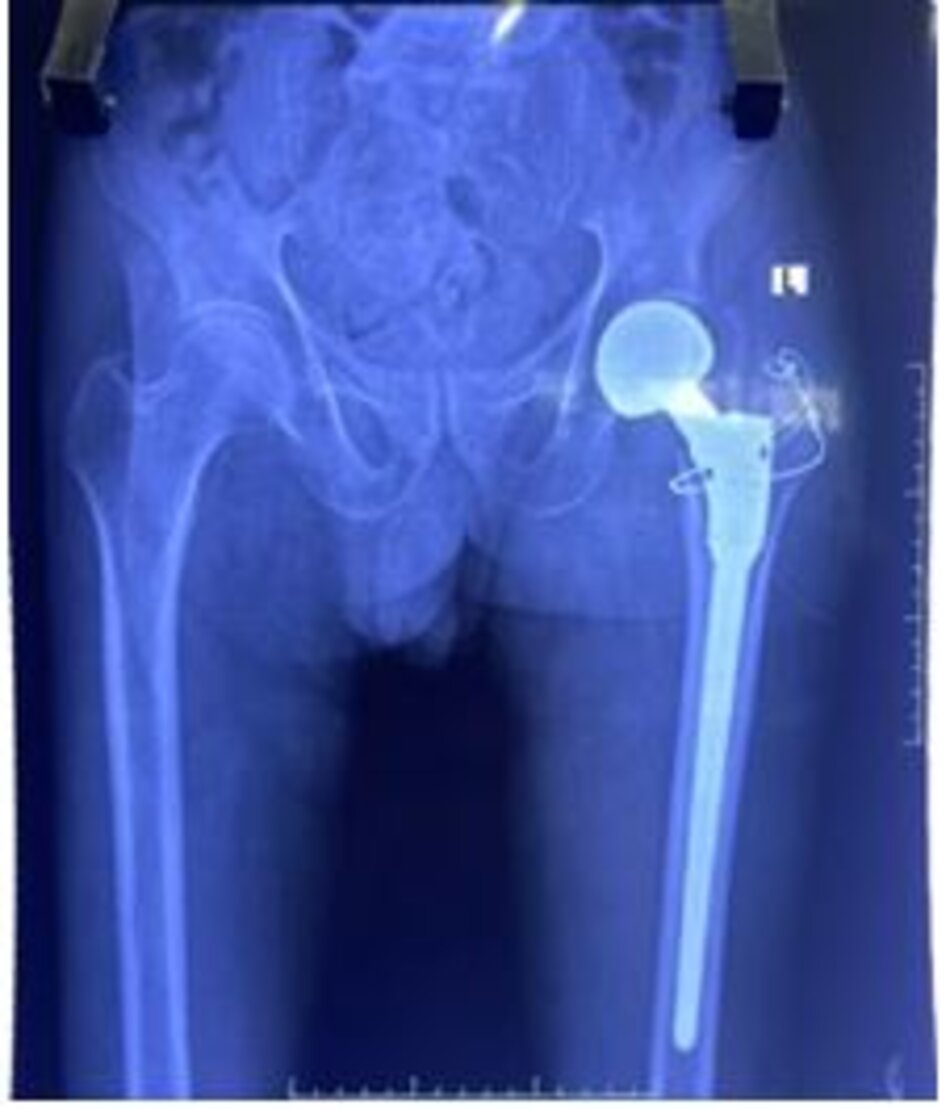

Thay khớp háng

Thay khớp háng toàn phần điều trị bệnh lý chỏm xương đùi – thoái hoá khớp háng

Bệnh lý viêm dính khớp háng/ viêm cột sống dính khớp

Xquang trước mổHình ảnh dính hoàn toàn khớp háng trái

BN nam 45 tuổi, viêm dính khớp háng 2 bên gây ra tình trạng khớp háng cứng chắc, không thể gấp duỗi

Xquang trước mổ. Hình ảnh dính hoàn toàn khớp háng trái. BN nam 45 tuổi, viêm dính khớp háng 2 bên gây ra tình trạng khớp háng cứng chắc, không thể gấp duỗi

Xquang sau mổHình ảnh khớp háng trái nhân tạo

Xquang sau mổ, BN đã có thể cử động khớp háng và tập đi lại ngày thứ 3 sau phẫu thuật

Xquang sau mổ. Hình ảnh khớp háng trái nhân tạo. Xquang sau mổ, BN đã có thể cử động khớp háng và tập đi lại ngày thứ 3 sau phẫu thuật